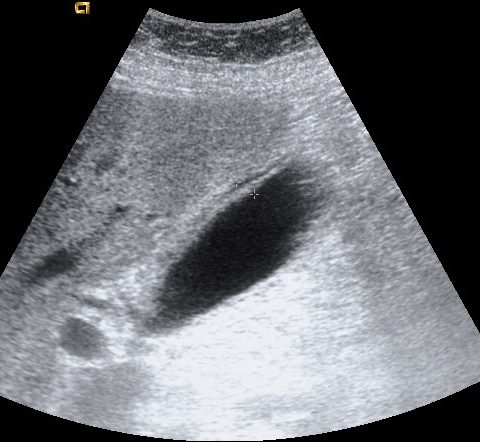

Se realiza ecografía abdominal:

Con estos hallazgos ecográficos podemos concluir que el paciente presenta una COLECISTITIS AGUDA.

ECOGRAFÍA:

Es la técnica de elección para el diagnóstico cuando se sospecha colecistitis (S y E > 95%, Robert et al.).

Criterios ecográficos de colecistitis (No existe consenso generalizado):

– Murphy ecográfico positivo y colelitiasis: es la combinación de signos ecográficos más predictiva de colecistitis aguda (VPP 92%). Puede resultar difícil observa la litiasis si ésta se localiza en el conducto cístico o en el cuello de la vesícula. Con engrosamiento mural el VPP aumenta al 94%)

– Otros signos secundarios son:

- Engrosamiento de la pared vesicular (>4mm) en ausencia de enfermedad hepática crónica, ascitis o insuficiencia cardiaca (el VPP asciende al 94%).

- Líquido perivesicular.

- Imágen de triple pared con capa hipoecoica central.

- Vesícula biliar distendida.

- Aumento de señal Doppler en la pared de la vesícula.

- Presencia de barro o material ecogénico en el interior de la vesícula.

Según la guía de Tokyo, el diagnóstico de colecistitis litiásica aguda puede hacerse cuando están presentes al mismo tiempo los siguientes hallazgos: engrosamiento de la pared vesicular mayor de 5 mm, líquido pericolecístico y Murphy ecográfico positivo. Otros signos son distensión vesicular, litiasis biliar, barro o material ecogénico biliar y gas en la pared. Sin embargo, debido a diferencias entre datos de frecuencia de sensibilidad y especificidad de los hallazgos individuales, el diagnóstico debe ser hecho a partir del análisis juicioso de los hallazgos individuales.